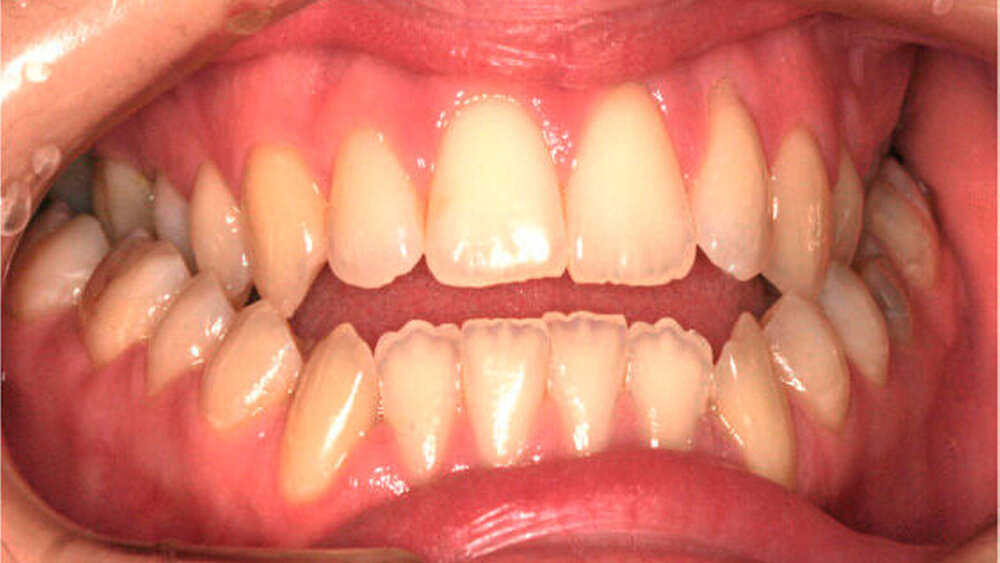

Die Patientin war zu Behandlungsbeginn 26 Jahre alt. Sie wies eine ausgeprägte skelettale Mesialbisslage (Wits: – 15,6 mm) mit retrognather Maxilla (SNA: 76°) und prognather Mandibula (SNB 87°) bei zusätzlicher Mittelgesichtshypoplasie auf (Abbildung 1a). Intraoral bestanden ein frontal offener Biss und eine transversale Enge im Oberkiefer mit zirkulärem Kreuzbiss (Abbildung 1b).

Sie wünschte eine Verbesserung der Kaufunktion, die durch den frontal offenen Biss und den negativen Overjet stark beeinträchtigt war. Ansonsten war sie mit sich und ihrem äußeren Erscheinungsbild zufrieden.